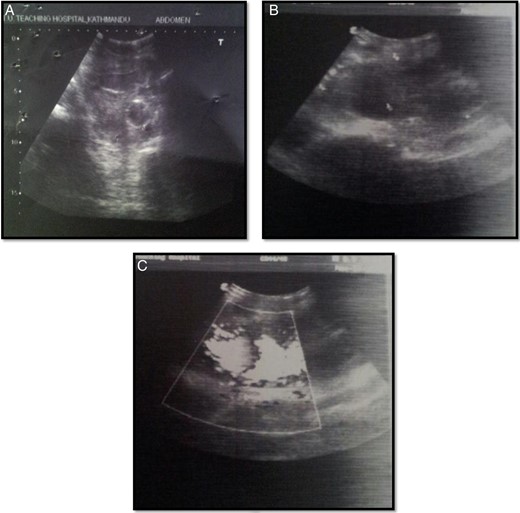

On contrast enhanced CT, a right common femoral pseudoaneurysm of size 12.5 × 6 × 6.5 cm was noted with intra-abdominal extension. Huge clot was also noted in the bladder with no obvious lesion in the kidney, ureter and bladder (Fig. 2). Thus, the patient was planned for exploration of pseudoaneurysm and urinary bladder. On exploration of right groin, there was a huge pseudoaneurysm in the groin extending above the inguinal ligament with 1 l of clot and blood (Fig. 3). Femoral artery was transected and proximal and distal ends were taken into control. Proximal end of femoral artery was ligated, and the leg was examined for distal saturation which was normal, so the distal end was also ligated. After addressing the femoral artery, the urinary bladder was explored. A small rent (∼0.5 × 0.5 cm) was noted in the right lateral wall of the bladder which was communicating with the wall of the pseudoaneurysm along with 2 l of blood and clot in the bladder. Thus, the enigma of hematuria was solved. Bladder was repaired according to standard technique and drain was kept in retroperitoneal space and abdomen was closed.

Axial CECT abdomen and pelvis pmages: (A) femoral pseudoaneurysm (marked with star), urinary bladder with clots (arrowhead) and Foley's catheter in situ (arrow); (B) communication between pseudoaneurysm and urinary bladder which was overlooked preoperatively (marked by arrow).